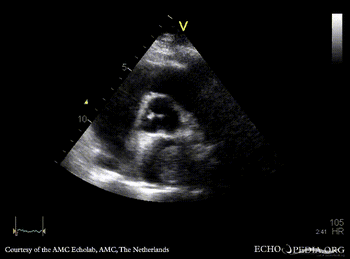

| PSAX: tumor mass in left atrium | A4CH |

| A4CH, zoom | |